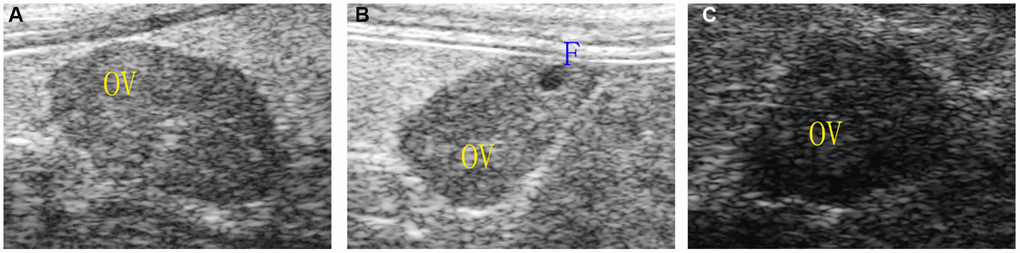

The ovarian area of the mice in the aging non-intervention group was smaller than that in the normal group (P = 0.0076), and the ovarian area in the aging intervention group was larger than that in the non-intervention group (P = 0.0210) (Figure 2, Table 1). The ovarian blood flow in the normal group was rich, the mice in the aging non-intervention group were weak or even disappeared, and the blood flow in the intervention group was richer than that in the non-intervention group (Figure 3). Pulse pressure, pulse index and resistance index were higher in aging non-intervention group than in normal group. After drug administration intervention, pulse pressure and pulse index decreased (Table 2).

Figure 2. Ovarian morphology under ultrasound. (A) Normal group; (B) Natural aging non-intervention group; (C) Natural aging intervention group; OV, ovary; F, follicle.